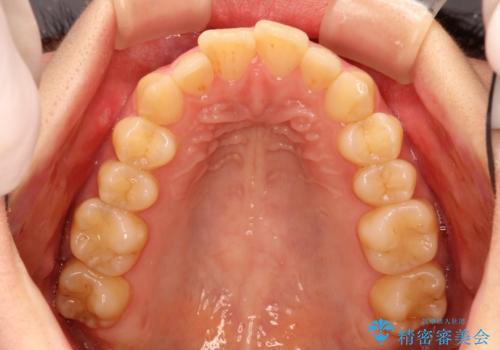

インビザラインにて上顎の歯を全体的に後方に移動させて前歯を引っ込める計画としました。

使用時間を守っていただけたので、比較的スムーズに矯正を終了することができました。